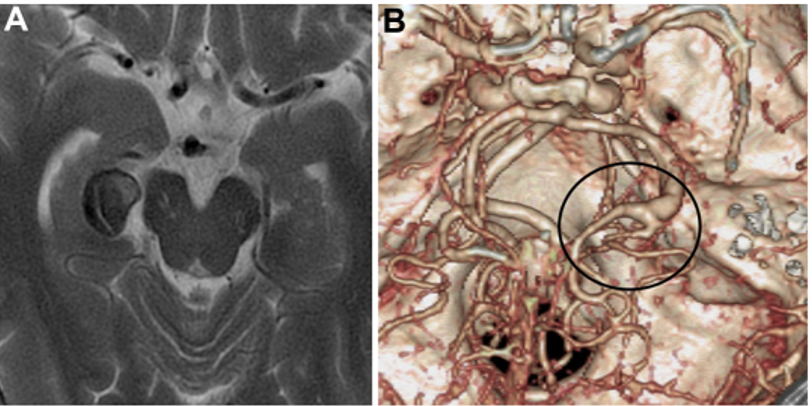

▼PTA在动脉瘤远端分支(图2A和2B)。予以右侧颞下入路手术,切除梭状回的一小部分被软膜,暴露动脉瘤顶端。随后,暴露动脉瘤的近端和远端颈,并识别PTA和P3段。

▼P3段被选为搭桥血管位置(图2C和2D)。如上所述,教授进行了STA-P3旁路手术并孤立动脉瘤。为了夹住动脉瘤,Kawashima教授使用了直长夹和有孔夹的组合,以避免P3段和PTA扭结。

▼此后,通过吲哚菁绿荧光血管造影证实旁路、P3段和PTA的通畅。Kawashima教授打开动脉瘤以确保其完全闭塞并继续进行血栓切除术。患者出院时没有出现任何神经功能缺损,并且在1年随访时,旁路仍然通畅,并成功通过手术孤立了动脉瘤(图2E和2F)。